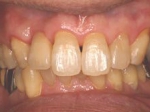

両側5歯症例

両側5歯症例両側5歯症例両側5歯症例 主訴-義歯のバネが壊れて手前の歯が痛んできた。 術前(旧義歯装着、鏡像) 術前(下顎粘膜面、鏡像)術前(下顎粘膜面、鏡像)術前(下顎粘膜面、鏡像) 術前レントゲン術前レントゲン術前レントゲン 術前口腔内(正面観)術前口腔内(正面観)術前口腔内(正面観)

術後(鏡像)術後(鏡像)術後(鏡像) 術後口腔内(正面観)術後口腔内(正面観)術後口腔内(正面観)もう入れ歯は要らなくなりました。 術後レントゲン術後レントゲン術後レントゲン